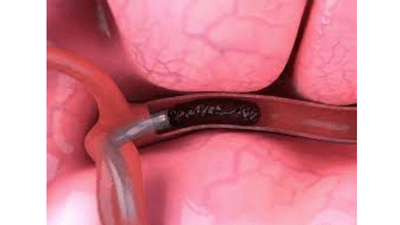

Report Oceanの最新調査によると、世界の神経トロンベクトミーデバイス市場規模は、2028年までに10億8670万米ドルに達する見込みです。レポート「神経トロンベクトミー装置市場 - 製品別(血栓回収装置、吸引・吸引装置、血管スネア)、エンドユーズ別(病院、救急クリニック、外来手術センター)、地域別、セグメント別予測、2028年」では、現在の市場ダイナミクスを詳細に把握し、今後の市場成長に関する分析を行っています。

例えば、2020年9月、ジョンソン・エンド・ジョンソン医療機器会社の米国拠点であるCERENOVUS社は、CERENOVUS Stroke Solutionsを導入することを発表しました。これら3つのデバイスに含まれるサービスは、欧州最小侵襲神経治療学会(ESMINT)で、外科医が血栓除去プロセスを効果的に行うことを支援するために設計されています。